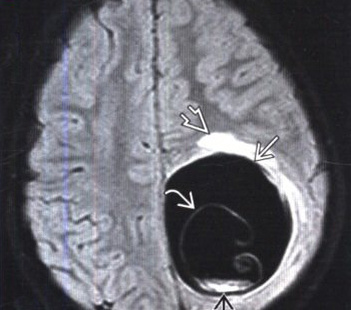

Вот так, например, выглядит на МРТ киста с личинкой в головном мозге